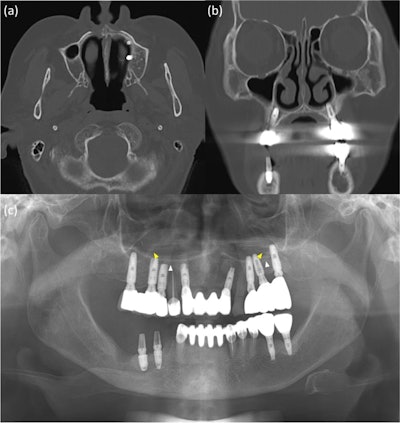

The x-ray and CT images of a 76-year-old woman. On the x-ray, white arrows indicate the hard palate line, while yellow arrows indicate the antral floor. Images of the implants in the left premolar and molar areas are superimposed above the hard palatal line. (b-c) The CT images revealed nasal floor perforation by an implant of the maxillary left premolar.

The woman had pain in the mandibular right posterior region and was diagnosed with osteomyelitis of the right posterior mandible based on clinical and imaging exams. CT images showed her dental implants had perforated the nasal floor of the maxillary left premolar.

However, panoramic x-rays revealed that the implants of the left maxillary premolar region were placed normally between the lateral wall of the nasal cavity and the faint medial wall of the maxillary sinus, the authors of the case study wrote.